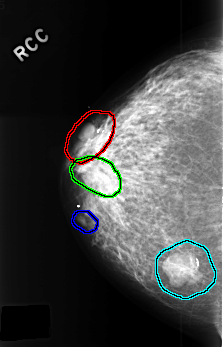

C_0384_1.RIGHT_CC

RIGHT_CC LINES 4504 PIXELS_PER_LINE 2888 BITS_PER_PIXEL 12 RESOLUTION 50 OVERLAY

FILE: C_0384_1.RIGHT_CC.OVERLAY

TOTAL_ABNORMALITIES 4

ABNORMALITY 1

LESION_TYPE MASS SHAPE OVAL MARGINS CIRCUMSCRIBED

ASSESSMENT 3

SUBTLETY 5

PATHOLOGY BENIGN

ABNORMALITY 2

ABNORMALITY 3

ABNORMALITY 4

LESION_TYPE MASS SHAPE LOBULATED MARGINS CIRCUMSCRIBED